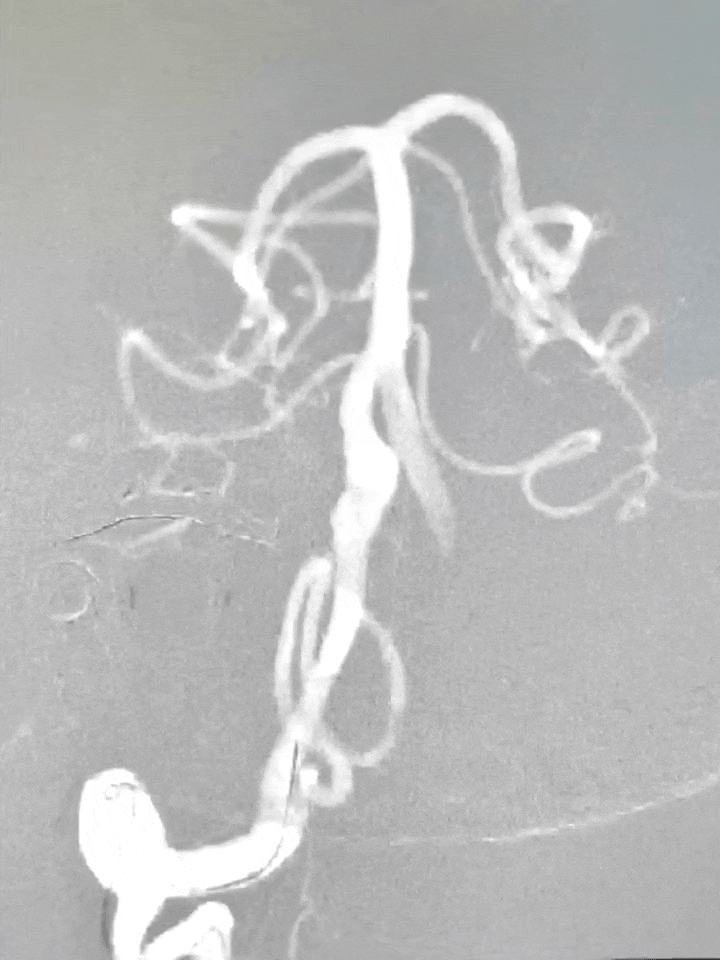

经桡动脉穿刺,132cm Simmons导管带7F 105 EasyRadial™输送导管过弓成攀超选右侧椎动脉。

132cm Simmons导管送至V2段末端输送导管。

微导丝带XT-27微导管至基底动脉尖。

将EasyRadial™输送导管送至V3段保持支撑。

造影测量血管直径3.5,选择4.0*30mm 密网支架释放。

密网支架释放完毕造影,显示支架打开良好。

将EasyRadial™输送导管撤至近端V2段动脉瘤处,释放7.0*40mm 血管支架。

血管支架释放完毕造影,手术结束。